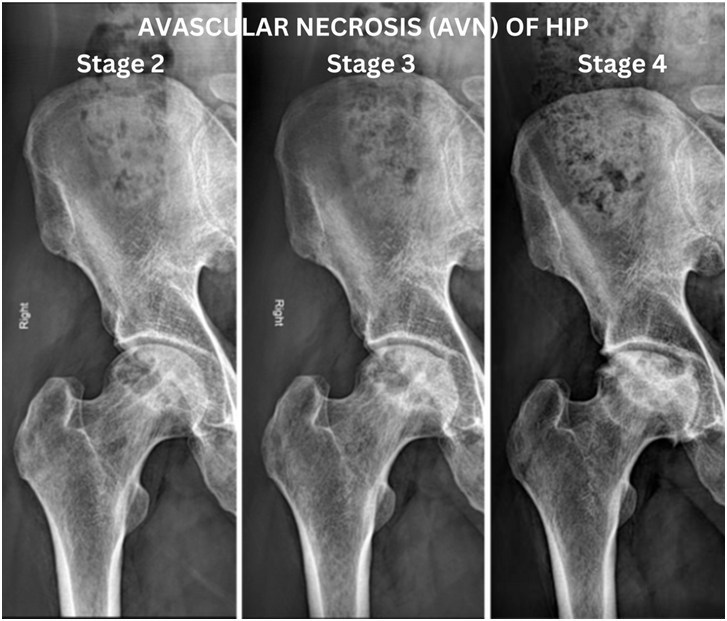

Avascular Necrosis (AVN), also known as Osteonecrosis, is a condition where the blood supply to the hip bone is reduced or completely cut off. Without enough blood, the bone tissue starts to die, leading to pain and joint damage. If left untreated, AVN can cause hip joint collapse, making movement difficult.

Early diagnosis is important to prevent joint damage. MRI, X-rays, and CT scans help detect AVN. Treatment options include: